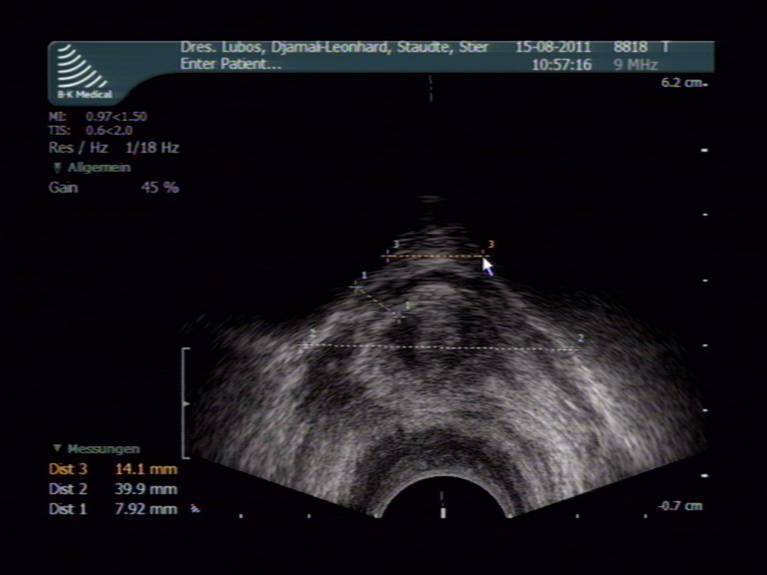

- Endo-Ultraschall mit farbcodierter Duplex-Sonographie und 3-D-Darstellung zur Vermessung, Gewebe- und Durchblutungsanalyse (Untersuchung aller anatomischer Strukturen des Damm-, Sitz- und Sattelbereiches wie Harnblase, Prostata, Harnröhre, After, äußeres Genitale, Nerven- und Blutbahnen sowie Becken- und Schambeinknochen)